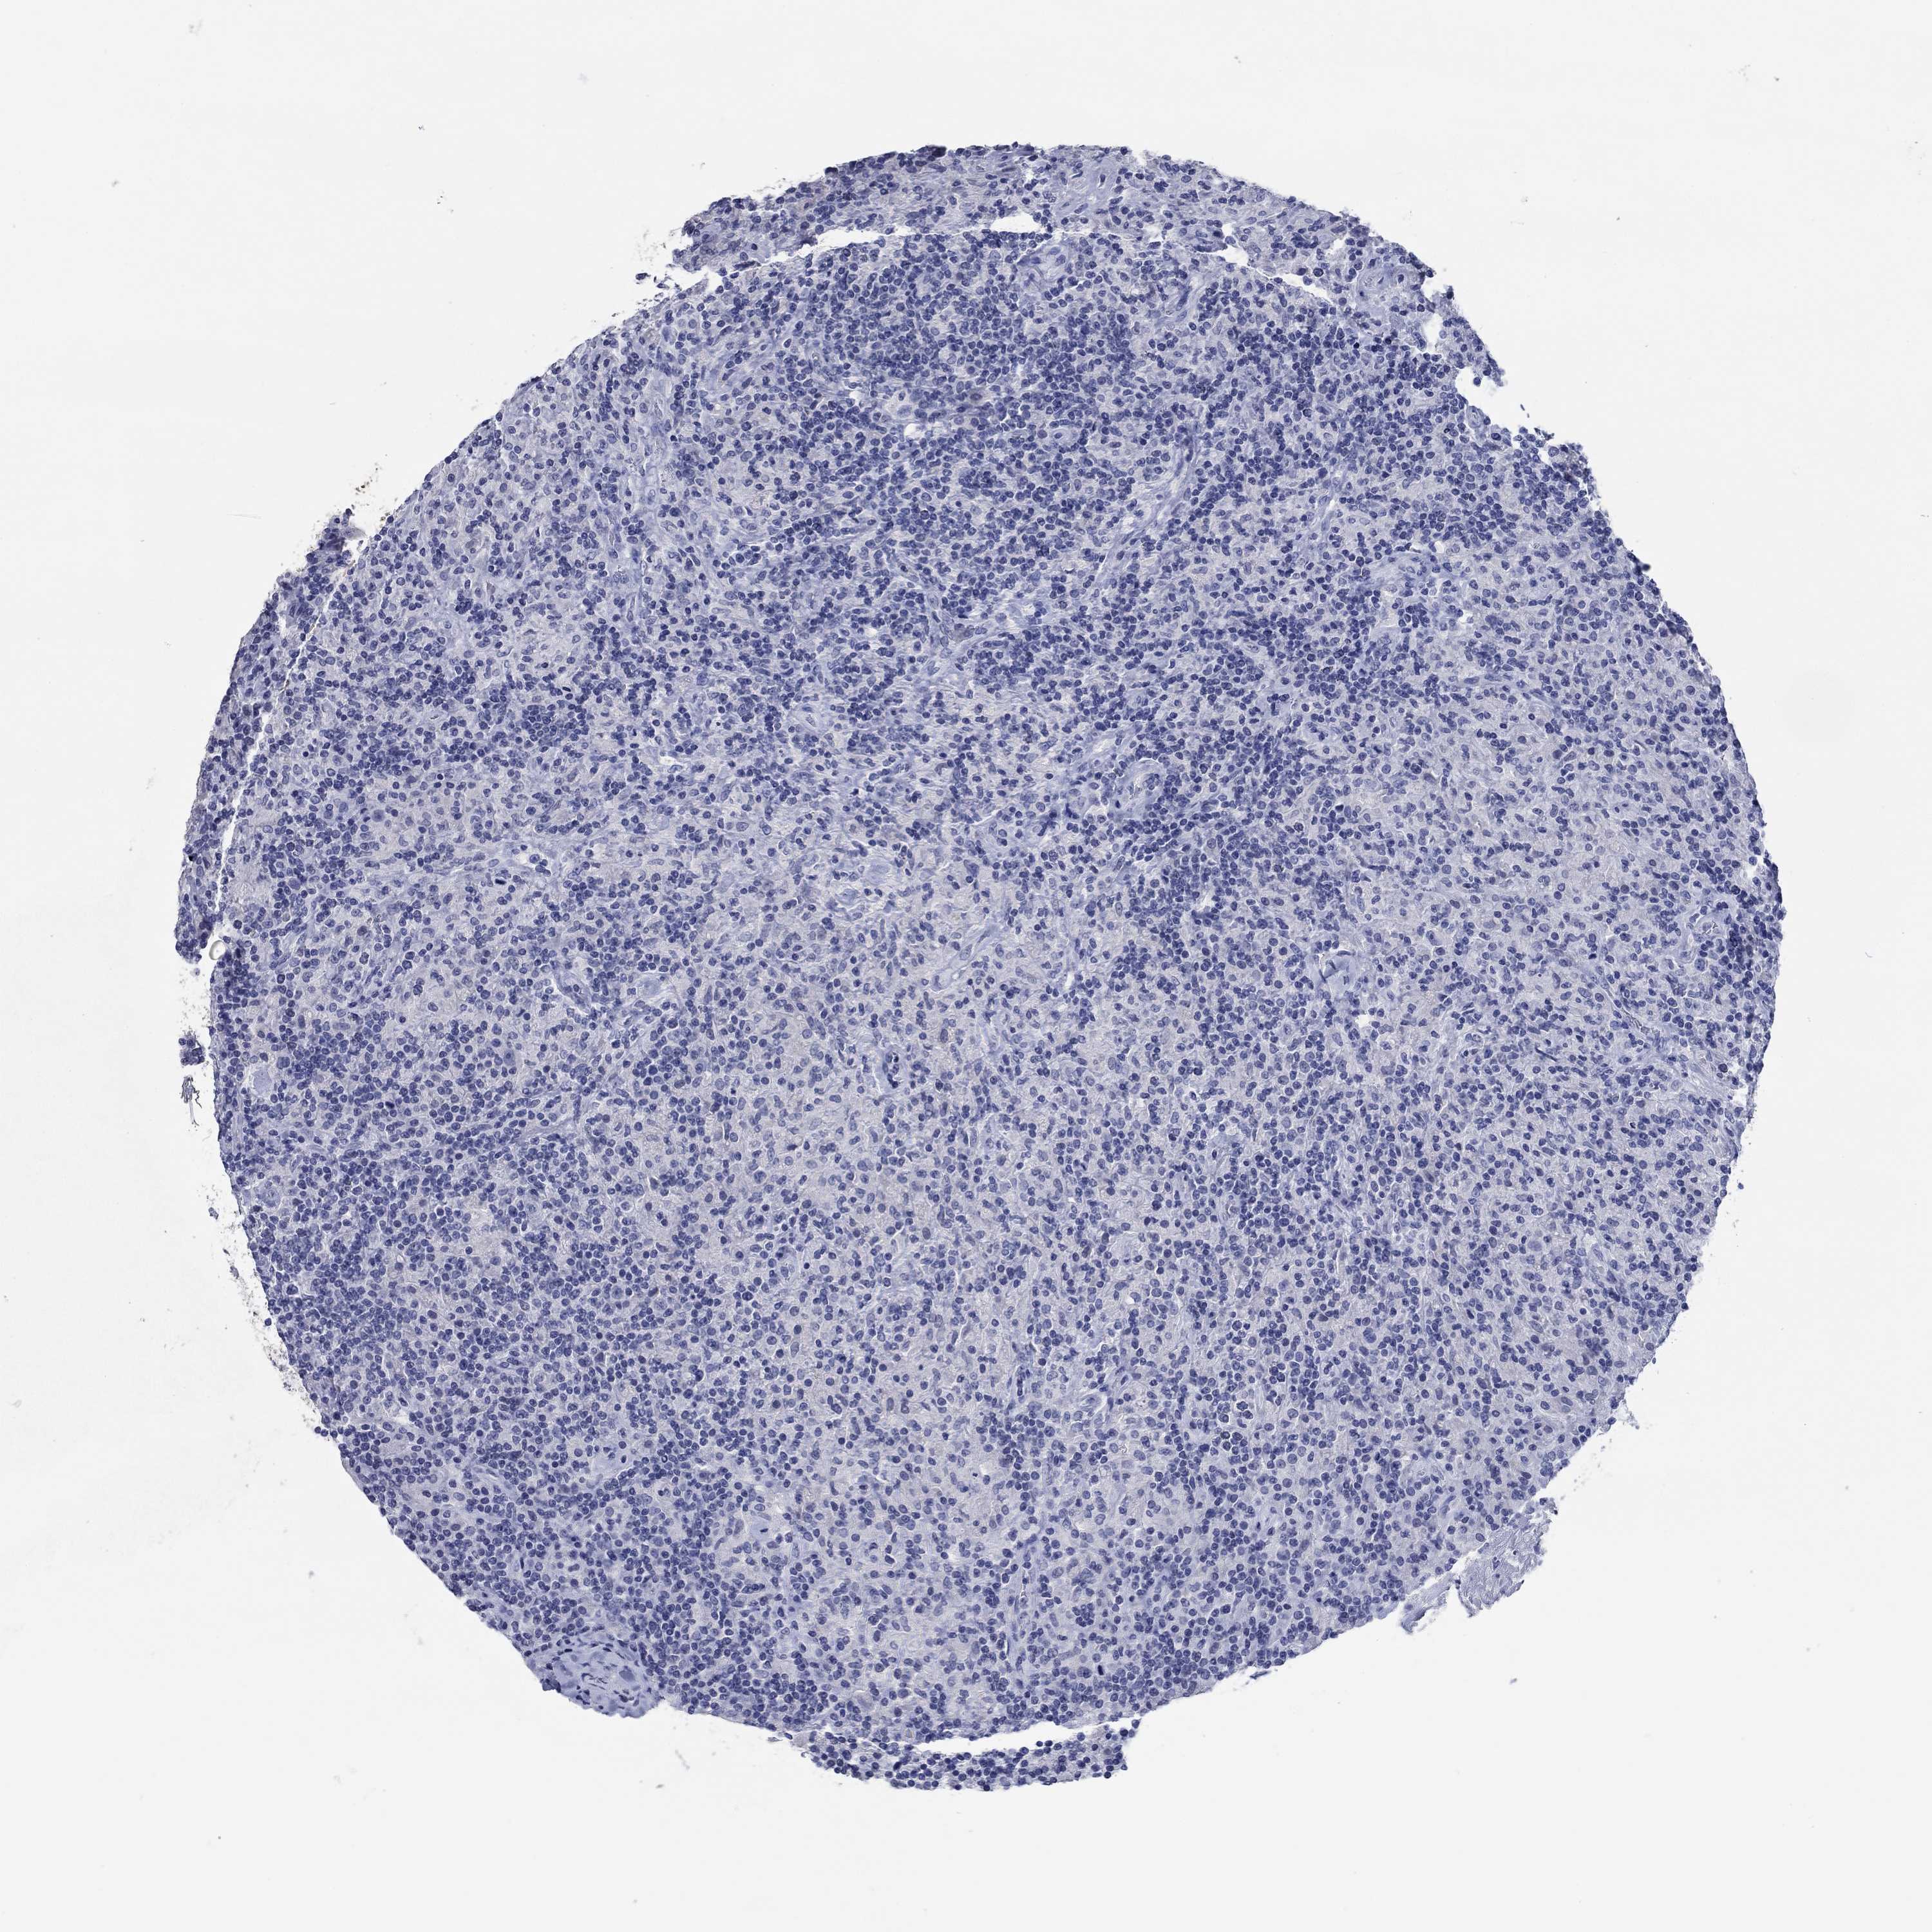

CANCER LYMPHOMA Show tissue menu

LYMPHOMA - Protein expressioni

A mouse-over function shows sample information and annotation data. Click on an image to view it in a full screen mode. Samples can be filtered based on level of antibody staining by selecting one or several of the following categories: high, medium, low and not detected. The assay and annotation is described here.

Each image is clickable and will lead to virtual microscopy that enables deeper exploration of all samples and also displays staining intensity scores, fraction scores and subcellular localization as well as patient and tissue information for each sample.

Antibody CAB025600

Antibody CAB026380

Antibody CAB079773

Staining

High

Medium

Low

Not detected

Intensity

Strong

Moderate

Weak

Negative

Quantity

>75%

75%-25%

<25%

None

Location

Nuclear

Cytoplasmic/membranous

Cytoplasmic/membranous,nuclear

Hodgkin's disease, NOS

Malignant lymphoma, non-Hodgkin's type, Low grade

Malignant lymphoma, non-Hodgkin's type, High grade